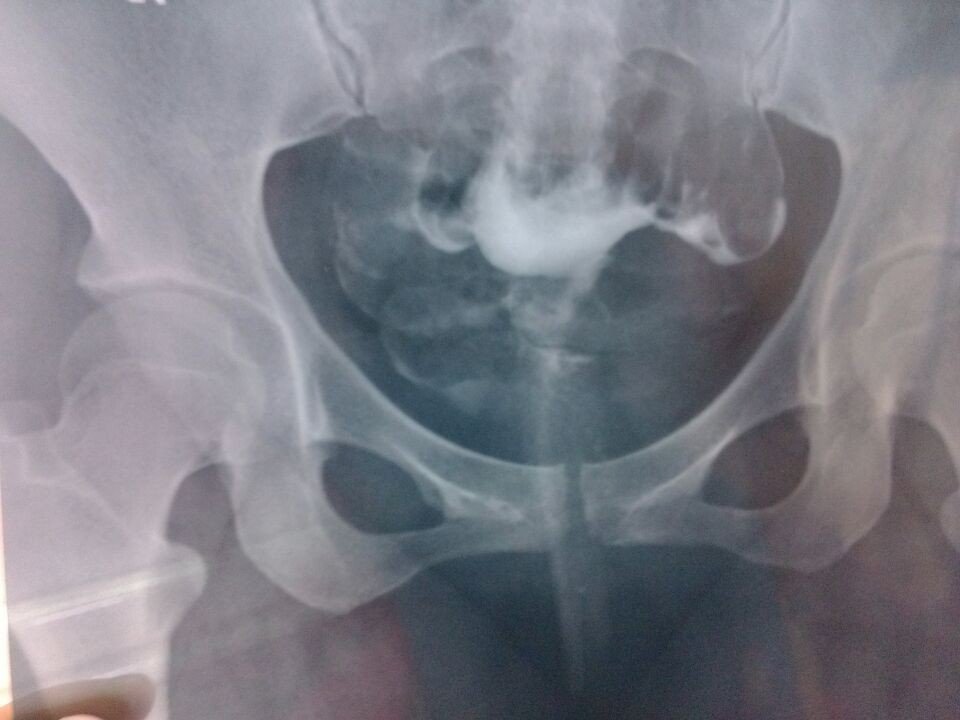

左侧输卵管各段未见对比剂弥散征象,10分钟后摄片,盆腔内见多量泛影葡胺弥散,呈团片状影,未见明显输 卵管淤积影, 诊断提示:1、右侧输卵管尚通畅2、左侧输卵管未显影,建议结合临床考虑3、慢性盆腔炎可能有19mm盆腔积液想请问一下医生,这个是不是左侧输卵管堵塞?要不要做手术?疏通左侧输卵管,谢谢 点击展开 匿名用户 2014-03-02 18:46 为您推荐: 其他回答 病情分析: 从你的检查结果来看是左输卵管堵塞的表现 指导意见: 从你现在的情况来看考虑是慢行盆腔炎症造成的输卵管堵塞,建议你考虑腹腔镜手术治疗 韩正思_SjH7 2014-03-02 19:04 相关问题 造影剂在盆腔呈片状、斑片状、索条状及结节状弥散,造影剂弥散欠佳,双侧输卵管疑有造影剂滞留 结婚多年一直不孕,去做了造影输卵管是通畅的,造影剂盆腔弥散不佳,医生让我回来等半年,半年过去了,这 子宫形态正常,输卵管左右通 造影剂进入盆腔 24小时弥散片示,弥散差,造影剂部分团